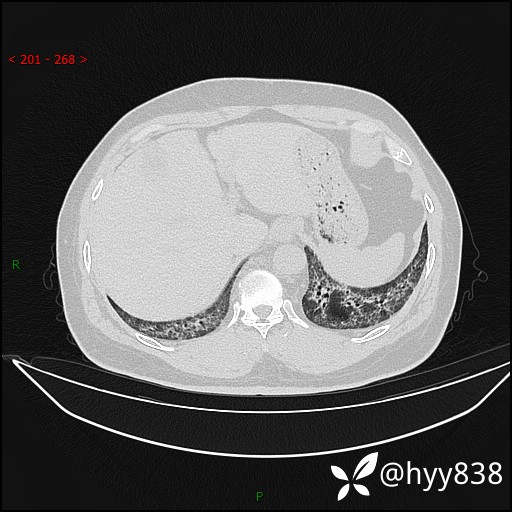

辅助检查:CT

临床诊断:间质性肺炎

第一次胸部CT